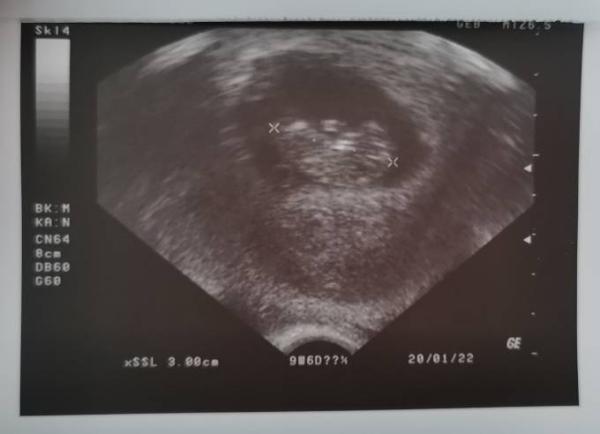

Gott sei Dank lief alles ganz gut. Der Ultraschall sah so aus, wie es aussehen sollte. Laut Messung sind wir exakt am 20.1. 22 ET geblieben.

Oh Melek, das freut mich total! Da hat sich deine Seile und Warterei ausgezahlt, man erkennt schon ein richtiges Baby ![]() Genieß die Erleichterung!

Du hast aber wirklich auch ein sehr schönes Bild

Du hast aber wirklich auch ein sehr schönes Bild ![]()

Was für ein schönes Bild und es freut mich sehr das bei dir alles gut ist. Wir sind auf den Tag genau gleich weit mit der Schwangerschaft und ich habe morgen meinen Termin bei meiner Frauenärztin und bin schon sooooo nervös ![]() Meine Symptome sind auch fast alle weg...irgendwie will man natürlich wissen ob alles gut ist aber irgendwie habe ich auch mega Angst vor morgen. Aber ich denke das ist normal.